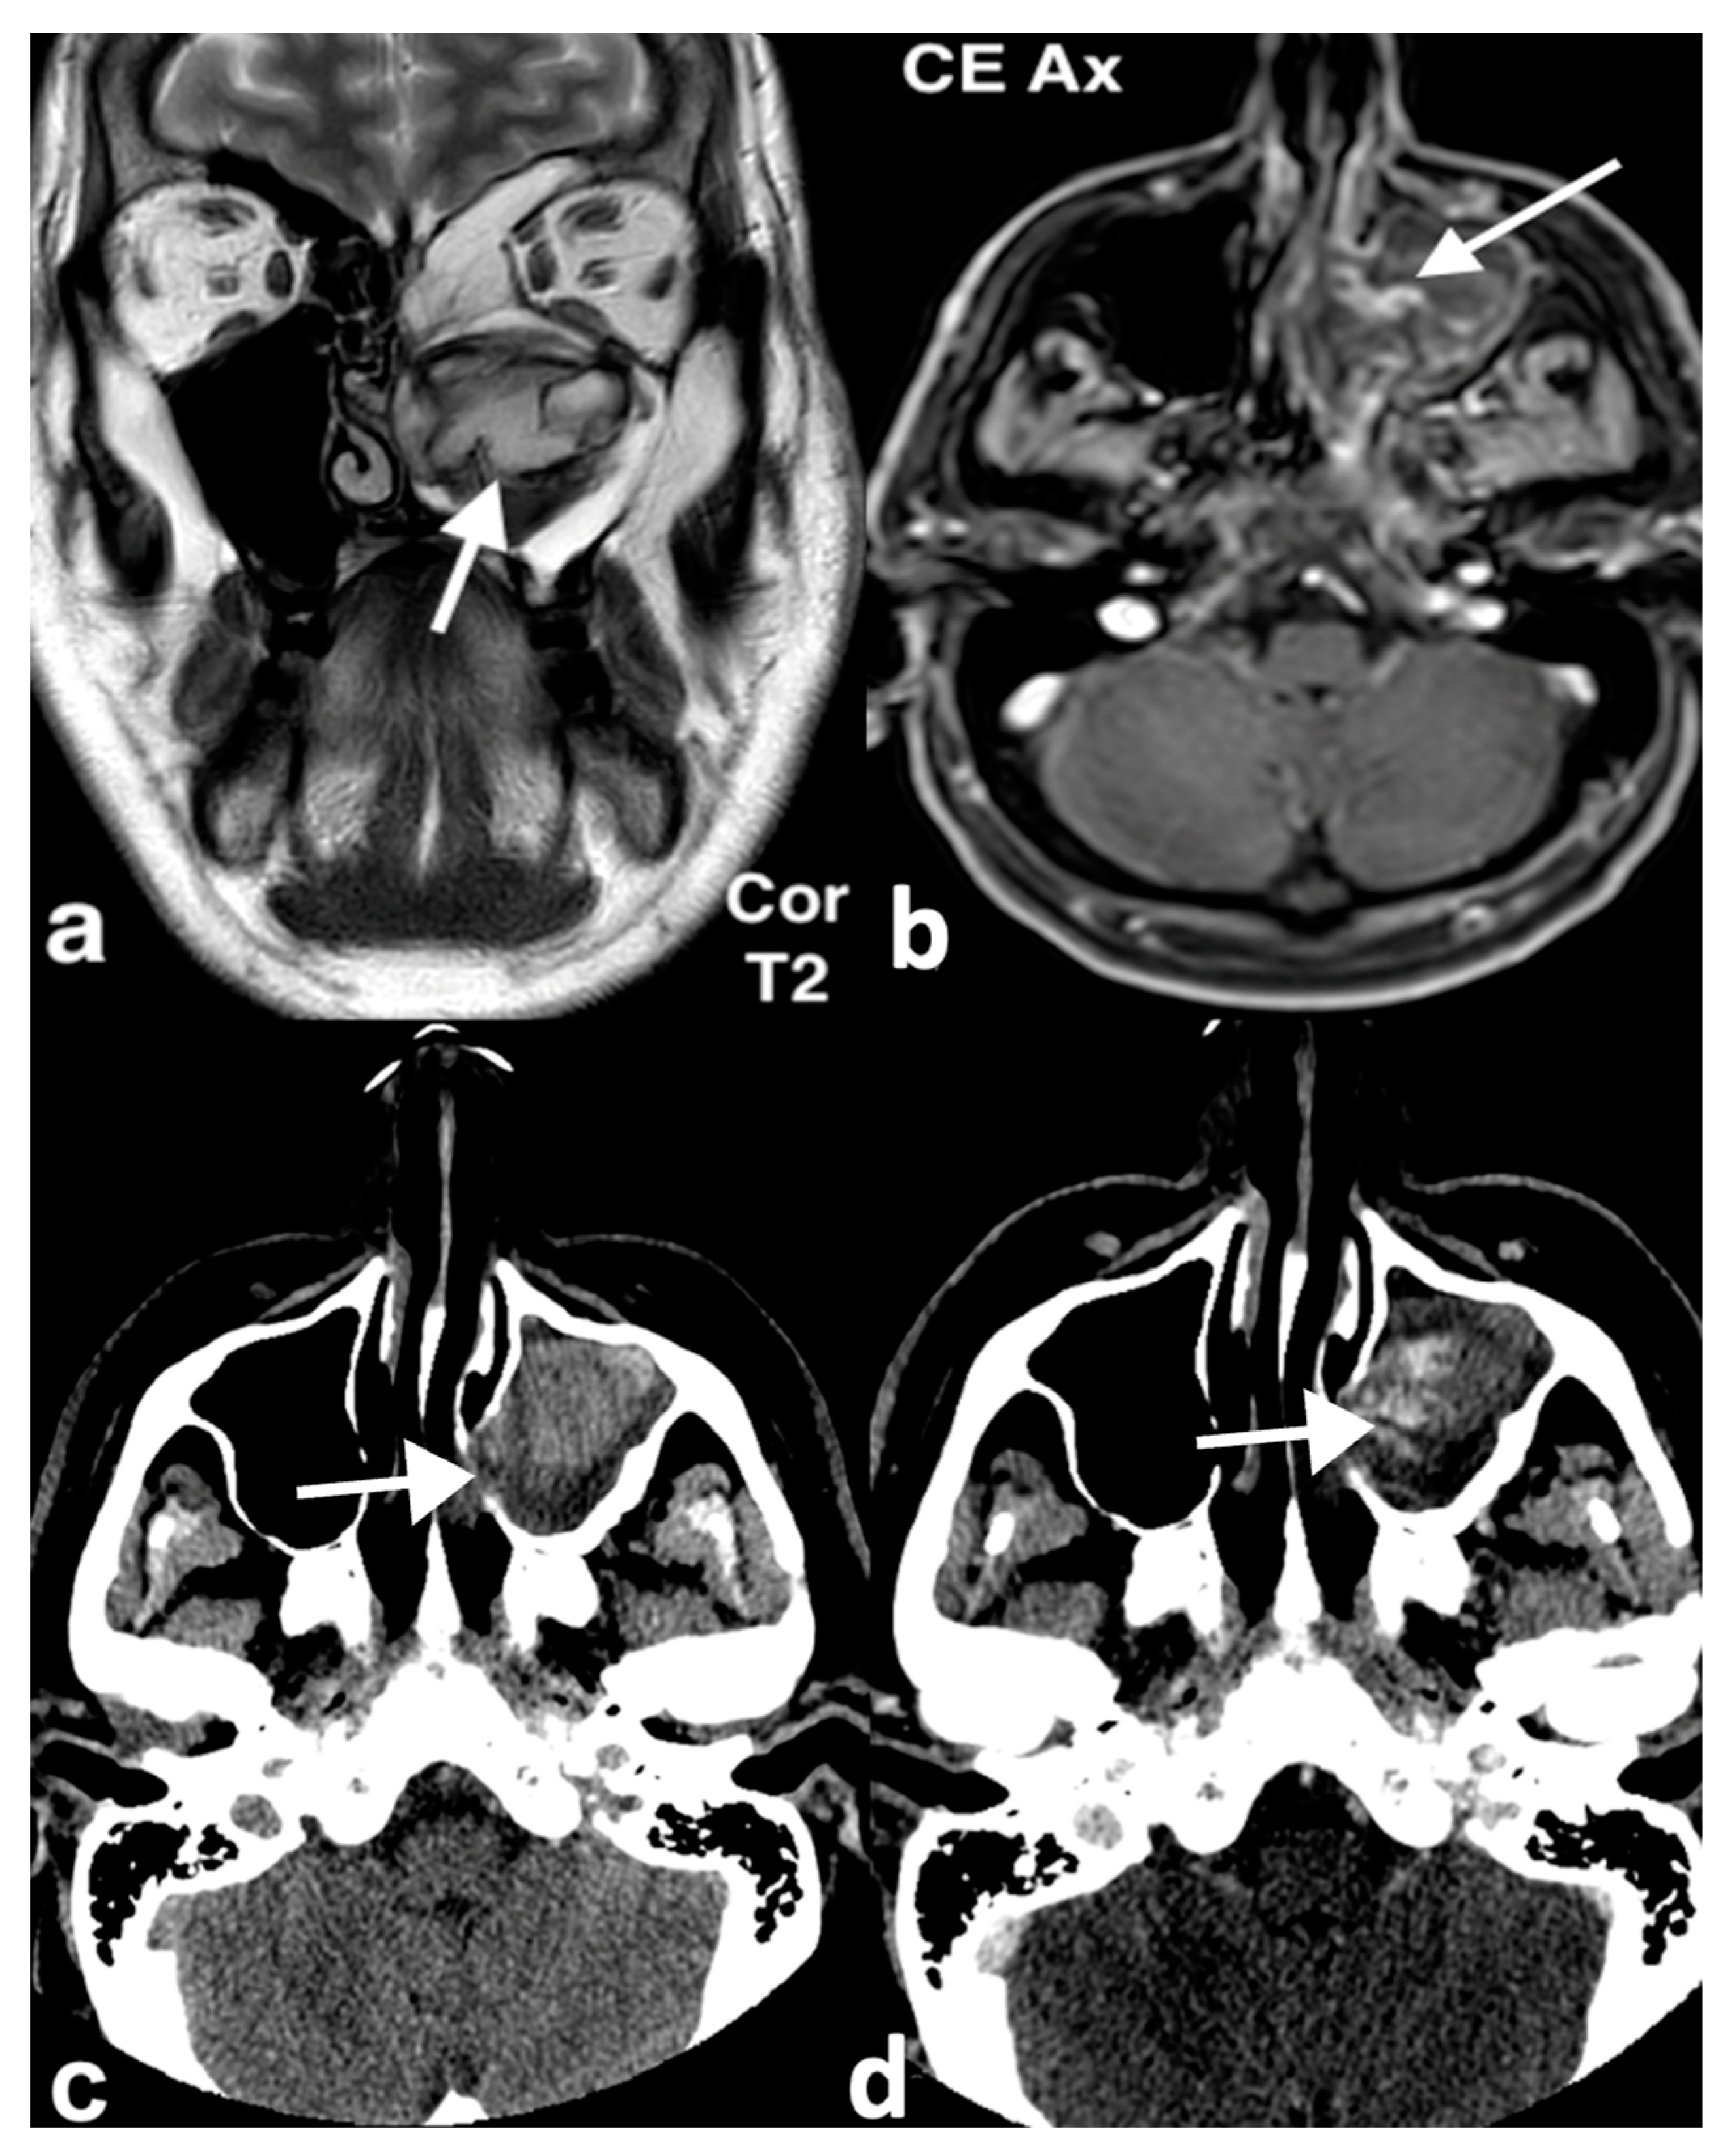

3.2.2. Chondromesenchymal Hamartoma

3.3.2. Esthesioneuroblastoma